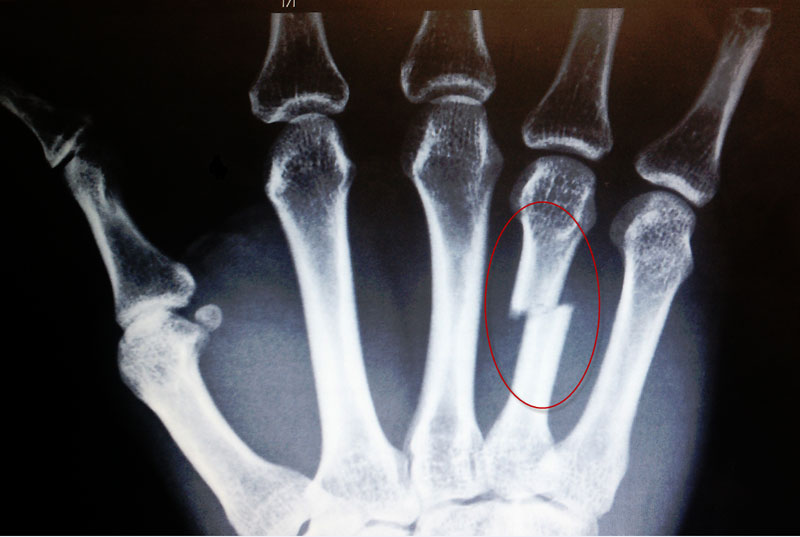

骨折是指人体在遭受直接暴力或间接暴力的情况下,使骨的连续性出现完全或部分的断裂。可发生于各个年龄段,以儿童和老年人多发。发生骨折后饮食调理是非常重要的,首先可以吃一些含钙高的食物,比如排骨、猪蹄、牛奶、豆制品、虾、蟹等,可补充骨折后身体的钙缺失。

1、及时检查清楚,进行固定,无论是石膏固定还是粉碎后的手术固定,一定要在医生的指导下,遵从医生的要求固定保护。

2、固定后要注意肿胀的情况,根据骨折的情况要注意治疗肿胀、软组织挫伤、感染或血管神经损伤。骨折的并发症需要早期检查清楚及时处理,否则单纯的骨折,即使固定后也不能很快的恢复良好。